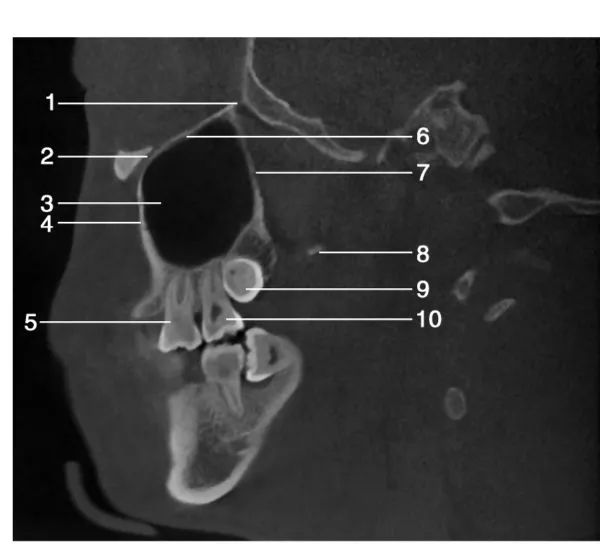

1.眶下裂( inferior orbital fissure) ; 2.眶下神经管( canal for infraorbital nerve) ; 3.上颌窦( maxillary sinus) ; 4.上颌窦前壁(anterior wall of maxillary sinus) ; 5.上颌第一磨牙( maxillary first molar) ; 6.眶底( floor of orbit) ; 7.上颌窦后壁( posterior wall of maxillary sinus) ; 8.翼突( pterygoid process) ; 9.上颌第三磨牙( maxillary third molar) ; 10.上颌第二磨牙( maxillary second molar)